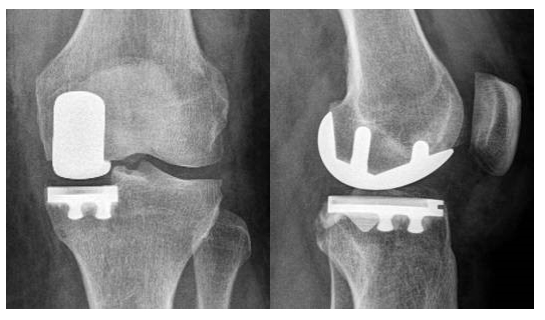

The half knee prosthesis or the unicompartemental knee replacement is placed when only part of the knee is worn (inside or outside). So not everyone qualifies for this. The big advantage of this type of knee prosthesis is that a large part of your own knee, including the cruciate ligaments, can be preserved. For patients, this means faster rehabilitation and a knee that feels more stable and more natural. Also in the long term, the half knee prosthesis has proven to last at least as long as the total knee prosthesis. A half knee prosthesis is also a valid option in the elderly if the indications are correct.

The patellofemoral prosthesis or the kneecap prosthesis is a kind of half knee prosthesis for people with isolated wear to the patellofemoral joint. The advantages are the same as for the half knee prosthesis: a large part of your own knee, including the tibiofemoral joint and the cruciate ligaments can be preserved.